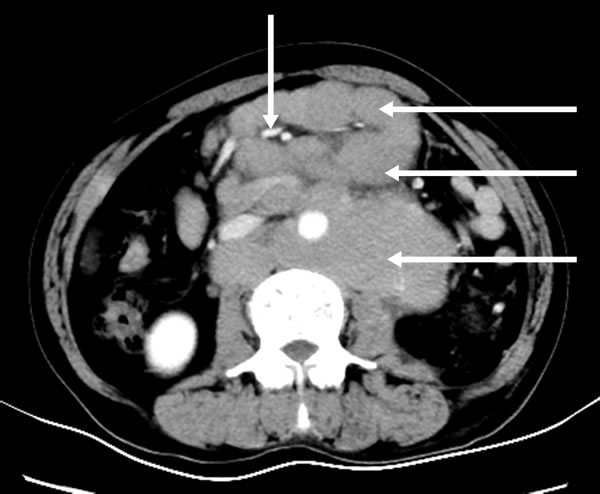

A 21-year-old male was hospitalized with a ten-month history of nasal blockage and a fever of one month duration. He presented with nasal blockage in the right side at the time of initial presentation, without nasal discharge, headache or tinnitus. Despite symptomatic treatment, he continued to do poorly and had persistent nasal blockage. He developed persistent fever a month ago, beginning at nightfall and peaking to 39 °C to 40 °C during the night or in the early morning. Meanwhile, a soy-like, painless and gradually increasing mass in the right submandibular area was found which was not responsive to antibiotic treatment. Fever improved when he received dexamethasone, and his temperature increased again when dexamethasone was withdrawn. Contrast computed tomography (CT) showed that the nasopharyngeal mucosa was thickened (Figure 1) and the celiac and retroperitoneal lymphaden was intumescent (Figure 2). Bone marrow aspiration and CT scan of chest and neck show normal. Finally, the biopsy based on nasal endoscopy and examination by flow cytometric methods confirmed a diagnosis of nasal NKTCL (Figure 3, Figure 4). According to the Ann Arbor staging, this patient was IIIB of the disease.

Figure 2: Contrast abdomen computed tomography shows multiple mesenteric and retroperitoneal lymph node enlargement and integration into masses with mild-middle enhancement, the mesenteric vessels embedded (sandwich sign).

Our patient has a soy-like, painless and gradually increasing mass in the right submandibular area, and has persistent fever beginning at nightfall and peaking during the night or in the early morning. Abdominal primary or metastatic malignant tumors often cause abdominal lymphadenectasis, such as gastric, liver, and colorectal cancer. Mesenteric lymphadenitis can also cause abdominal lymphadenectasis which mainly occurs in children and is usually accompanied with secondary acute upper respiratory tract infection. A CT scan showed mesenteric and retroperitoneal lymphadenectasis. Tuberculous lymphadenitis could occur in the neck, armpits, abdomen and groin. In the early stage, patients commonly present with painless swollen lymph nodes. Some patients experience low-grade fever and night sweats. However, lymphoma is a common cause of lymphadenectasis, of which clinical symptoms are non-specific, although fever is common. Infection, malignancy, collagenous vascular disease could cause fever of unknown origin (FUO). These diseases are usually hidden, and accompanied by atypical symptoms, such as subacute bacterial endocarditis, perforation of the retrocecal appendix, pericolonic abscess, occult liver or splenic abscesses, and prosthetic graft infections, which may easily be missed and eventually present as an undiagnosed prolonged fever [10-12].